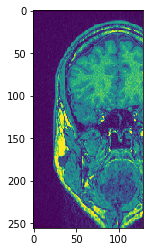

Utilice subplots para ponerlos uno al lado del otro

fig, axs = plt.subplots(1, 4, figsize=(15, 7))

cle.imshow(transposed_image[75], plot=axs[0])

cle.imshow(transposed_image[100], plot=axs[1])

cle.imshow(transposed_image[125], plot=axs[2])

cle.imshow(transposed_image[150], plot=axs[3])